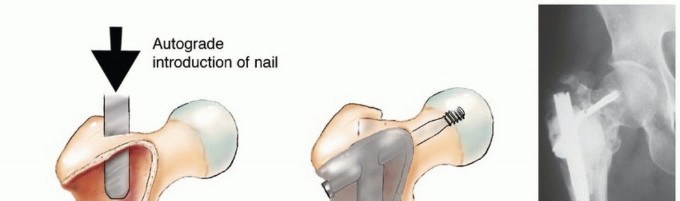

الشكل 1: أ. صورة أشعة سينية تظهر ورمًا نقيليًا في الحُق الأيمن لدى رجل يبلغ من العمر 72 عامًا ولديه تاريخ معروف بسرطان الغدة الدرقية. ب. يظهر التصوير المقطعي المحوسب (CT) تدميرًا واسعًا للعظام وامتدادًا للأنسجة الرخوة. محاولة الاستئصال بناءً على النتائج الشعاعية وحدها قد تؤدي إلى استئصال جزئي للآفة ونزيف محتمل بسبب الأوعية الدموية الكثيفة لهذا الورم. بالنظر إلى هذه النتائج الشعاعية، خضع هذا المريض لانسداد وعائي قبل الجراحة مما قلل من فقدان الدم أثناء الجراحة وسمح باستئصال ناجح.

الشكل 2: أ. صورة أشعة سينية تظهر كسرًا مرضيًا في الورك لدى أنثى تبلغ من العمر 69 عامًا ولديها تاريخ معروف بسرطان الثدي. ب. أجريت عملية استبدال نصفي للورك خلال 24 ساعة من حدوث الكسر، ولكن صور الأشعة السينية بعد الجراحة أظهرت نقيلة إضافية أسفل طرف جذع الطرف الاصطناعي (ج) لم يتم اكتشافها بسبب سوء جودة صور الأشعة السينية قبل الجراحة ولأن صور الأشعة السينية للعظم بالكامل لم تُجرَ قبل الجراحة. د. بينما كانت لا تزال في المستشفى، عانت من كسر مرضي في تلك الآفة أثناء نقلها من سريرها إلى كرسي استلقاء.